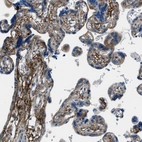

Immunohistochemistry analysis in human placenta and liver tissues using HPA017759 antibody. Corresponding FBN1 RNA-seq data are presented for the same tissues.